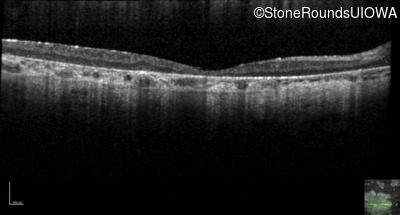

| AR Stargardt Disease | ABCA4 | Cys205Phe TGC>TTC | Gly863Ala (G)GA>(G)CA | AR |